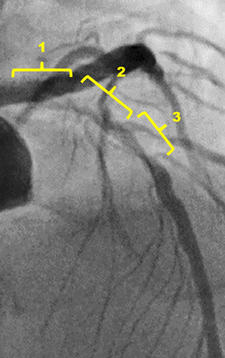

Diagnostic angiography

RCA shows diffuse atherosclerosis stenosis lesion, especially at the ostium.

The left coronary artery indicated 90% stenosis with severe calcification from the proximal to the middle part of LAD and diagonal branch

Target lesion: LAD middle part, Medina (1,1,1)